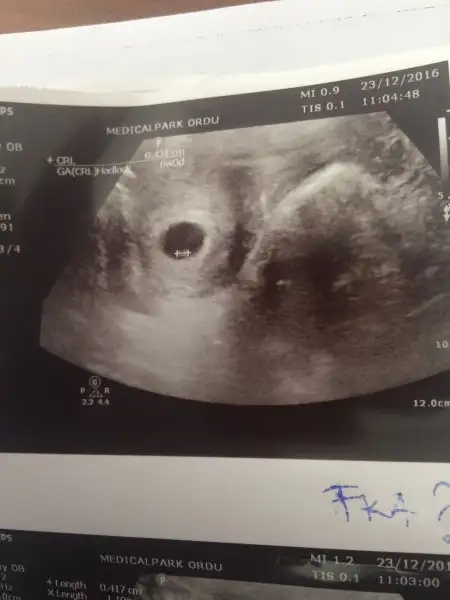

KIZLAR MERHABA 7+3 RESMIMIZ YORUMLAR MISINIZZ

BIRINDE SOLDA GORNUYOR. ERKEK DIYORLAR SOL OLUNCA AMA BILEMIYORUM TAMDA. KALP ATISI NASIL ?

BENIMDE AYNI OLDU HATTA KORKTUK BISEYMI OLDU DIYE AMA MINIK OLDUGU ICINMIŞ :) 7. HAFTADA GİTTİK PIT PIT ATIYODU KALBI :) KALP ATIS HIZINA GOREDE KIZ ERKEK DIYORLAR AMA DOKTORA SORDUM ALAKASI YOK DEDI.140 ALTI ERKEK ÜSTÜ KIZ DEMISLERDI BNA. BENIMKIDE 105 :)

Evet canım çokta kafama takmıyorum haftaya dahadaa büyümüş olacak inşallah bebeğim, kalp atışına göre cinsiyet tahmini yapılıyor kimşsi de tutuyor bakalım bende bugün sordum ısrarla hızını ama atıp atmadığı belli değil dedi, sen erkek mi istiyosun canım